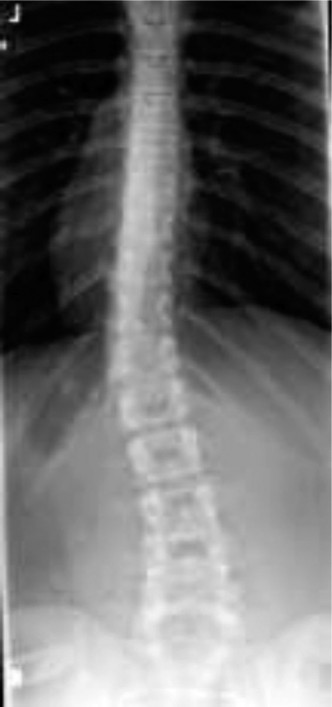

Pediatric scoliosis encompasses a spectrum of spinal deformities characterized by a three-dimensional deviation of the vertebral column. Clinically, it presents with lateral curvature in the coronal plane, rotation in the axial plane, and alterations in the sagittal plane. Affecting approximately 2-3% of adolescents, the most prevalent form is Adolescent Idiopathic Scoliosis (AIS), typically presenting after 10 years of age. Other etiologies include Early-Onset Scoliosis (EOS) – defined as onset before 10 years of age, congenital scoliosis resulting from vertebral malformations, and neuromuscular scoliosis associated with conditions like cerebral palsy or muscular dystrophy. Syndromic scoliosis, linked to conditions such as Marfan's or neurofibromatosis, represents another distinct category.

- Vertebral Anatomy: Each typical vertebra comprises a body, pedicles, laminae, and posterior elements (spinous and transverse processes, articular facets). In scoliosis, these structures undergo characteristic adaptive changes, including vertebral body wedging, pedicle elongation and thinning on the convex side, and compensatory rotation. The Cobb angle, while a primary measure of coronal deformity, fails to fully capture the 3D nature, which includes rotational deformity and often a flattened thoracic kyphosis or compensatory lumbar lordosis.

Thorough preoperative planning is the cornerstone of successful deformity correction. The radiographic evaluation must include high-quality, full-length standing posteroanterior (PA) and lateral radiographs of the spine, extending from the occiput to the pelvis to assess global coronal and sagittal balance. Flexibility films—such as supine side-bending, fulcrum bending, or traction radiographs—are critical for differentiating structural from non-structural curves, directly influencing the selection of the upper and lower instrumented vertebrae (UIV and LIV).